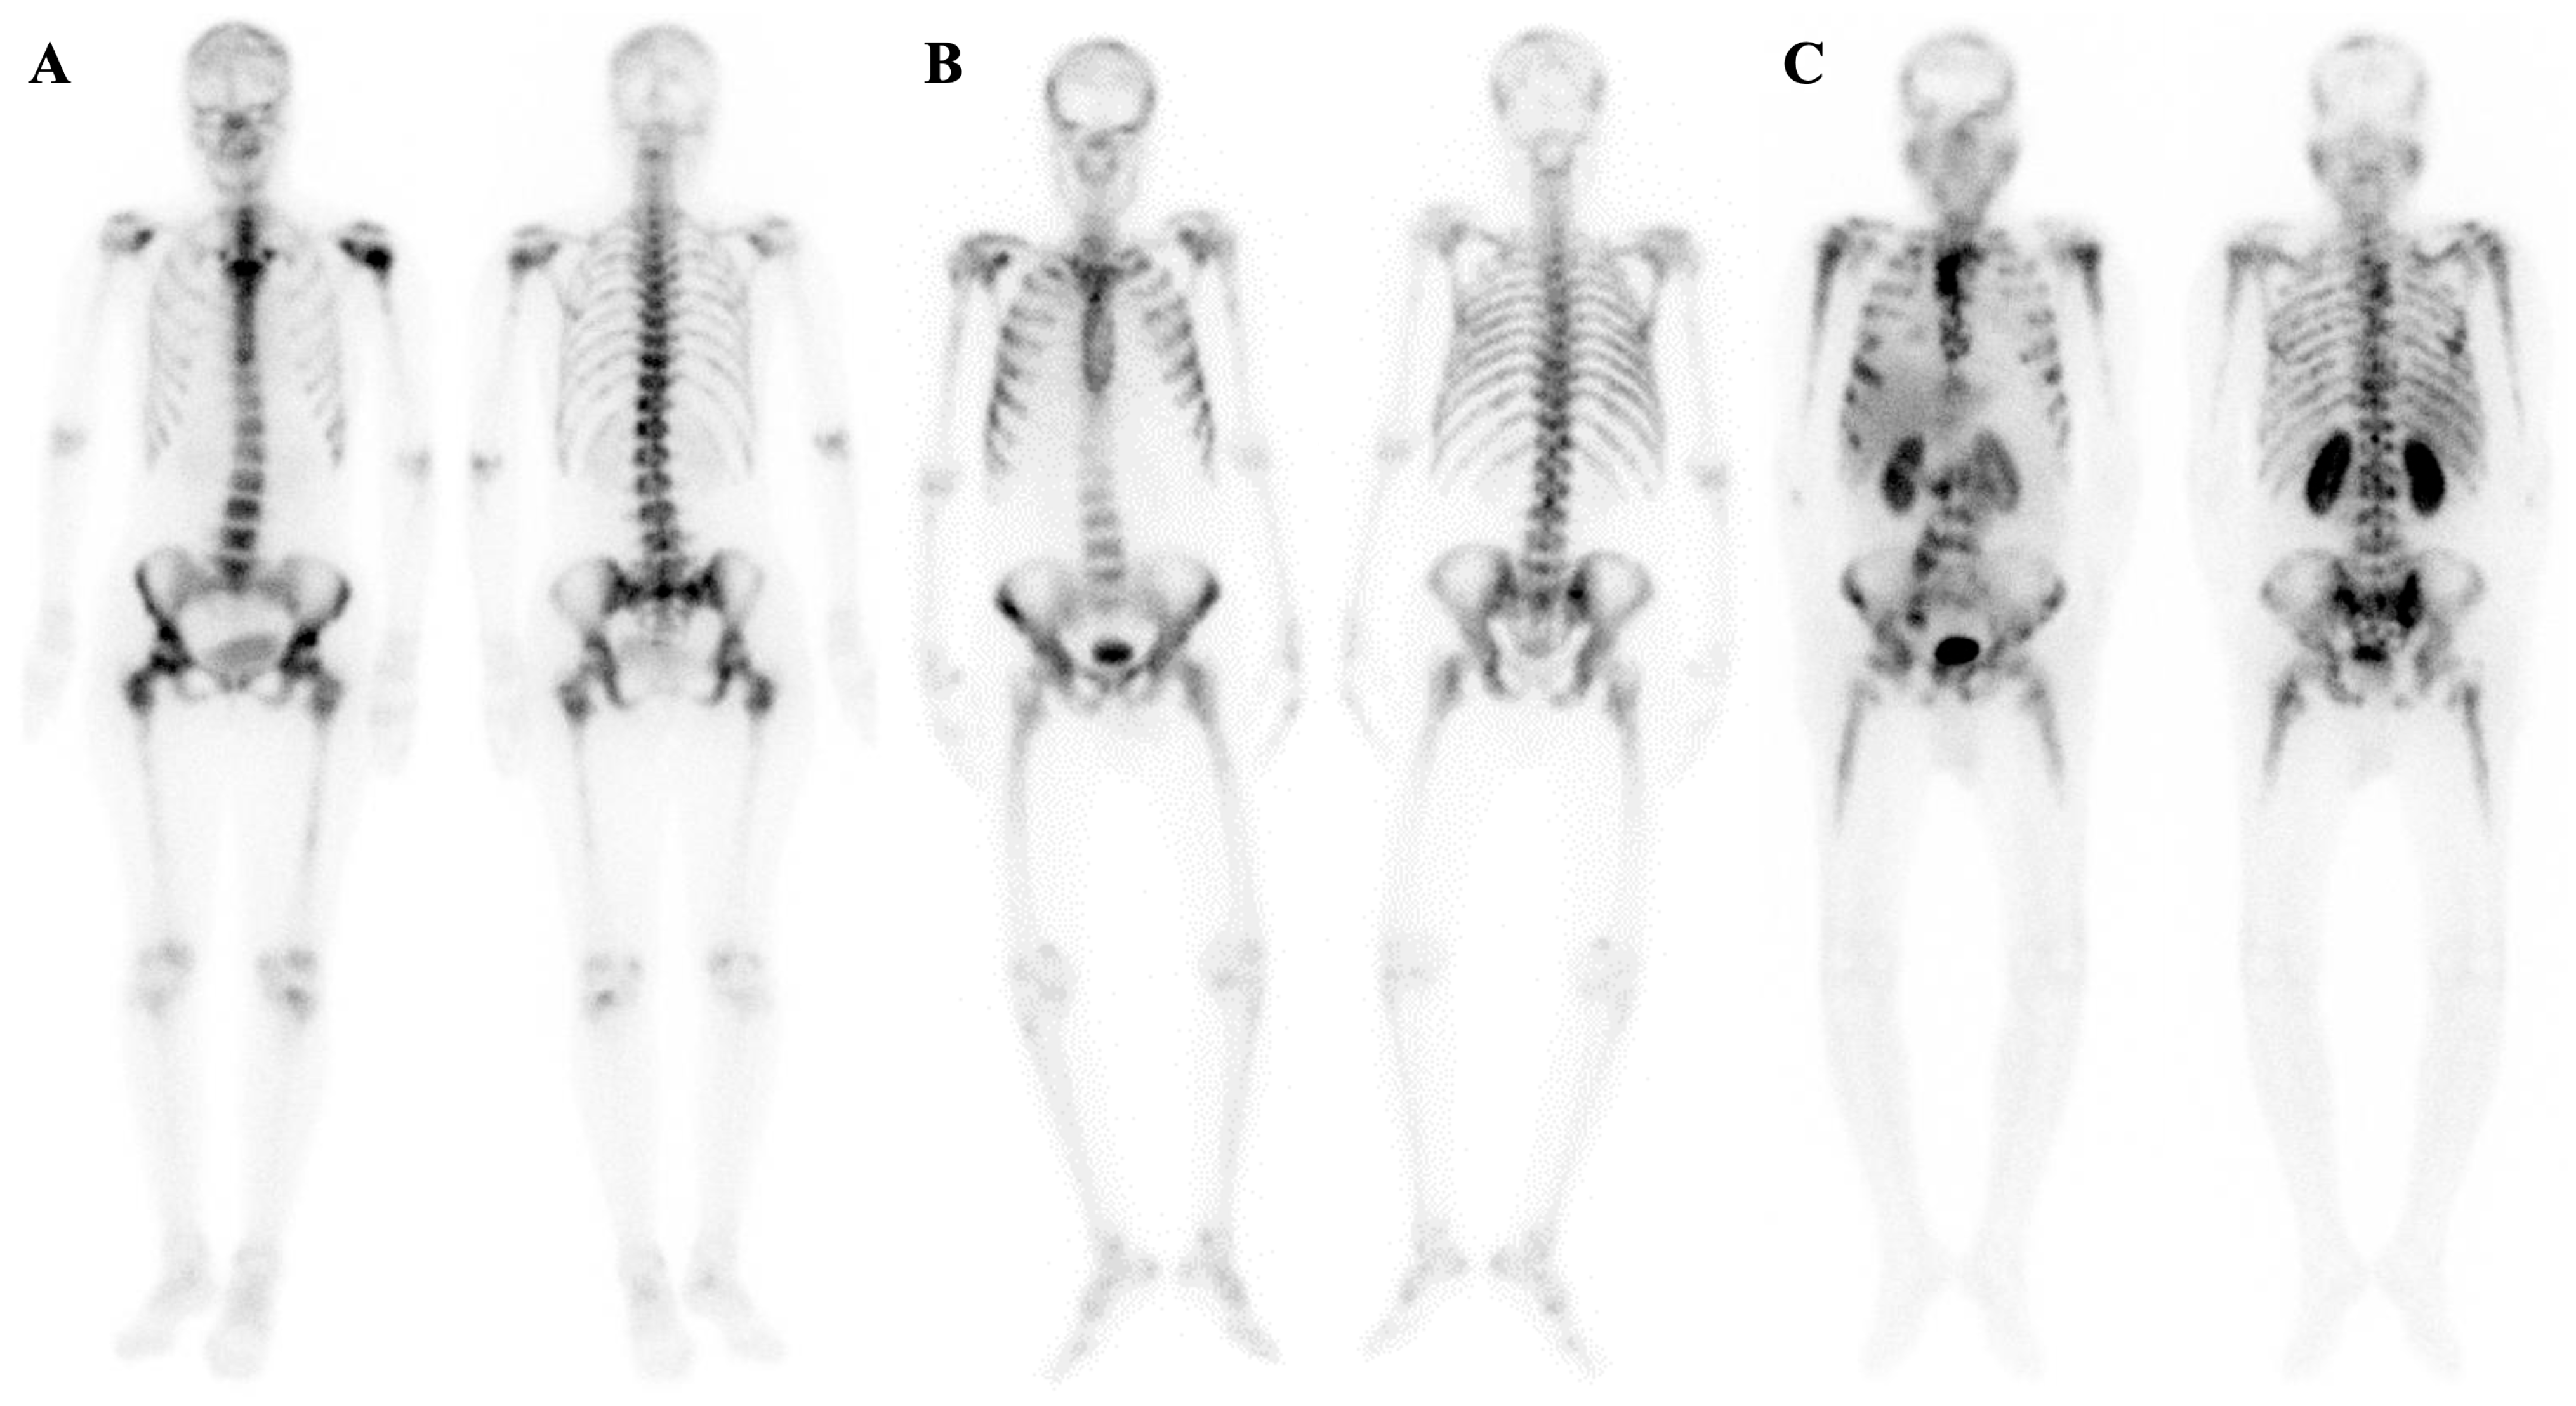

7.2. Metabolic Superscan

7.3. Distinguishing Metabolic Superscan from Metastatic Superscan